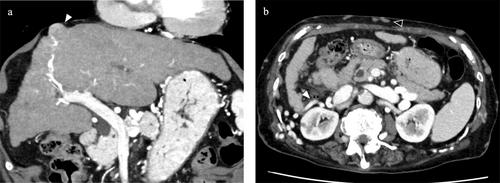

Budd-Chiari综合征(BCS)由静脉流出梗阻引起,可导致肝脏充血和门静脉高压症。BCS还与相对较高的肝细胞癌(HCC)发病率相关。选择一种基于血流动力学评估的微创方法来治疗BCS引起的HCC是至关重要的。一例88岁女性BCS患者发现肝脏肿瘤位于肝8节区。在详细的术前血管造影血流动力学评估后,成功实施了胸腔镜经胸肝切除术(TTH)。对于包括BCS患者在内的高危HCC患者,TTH可能是一种可行且有效的手术选择。

Budd-Chiari syndrome (BCS), caused by venous outflow obstruction, results in hepatic congestion and portal hypertension. BCS is also associated with a relatively high incidence of hepatocellular carcinoma (HCC). Selecting a minimally invasive approach based on hemodynamic assessment for the management of HCC arising from BCS is essential. A hepatic tumor located in liver segment 8 region was identified in an 88-year-old female patient with BCS. Following a detailed preoperative hemodynamic evaluation using angiography, a thoracoscopic transthoracic hepatectomy (TTH) was successfully performed. TTH may represent a feasible and effective surgical option for HCC in high-risk patients, including those with BCS.